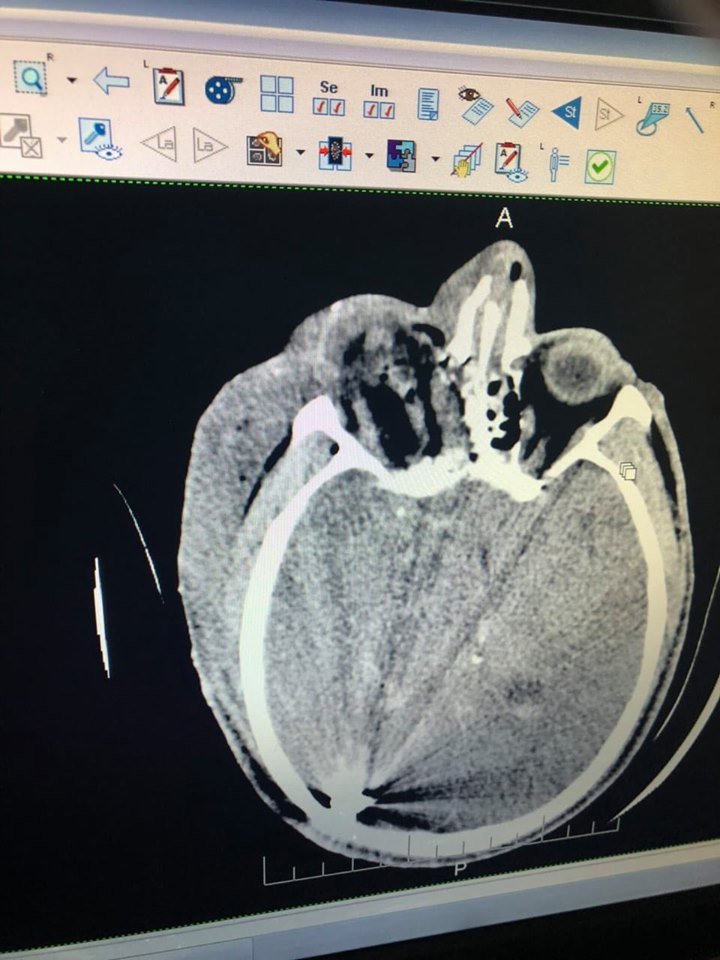

"Андрею 33, солдат из Николаева. Получил ранения сегодня у Водяного. Тяжелое минно-взрывное ранение, проникающее ранение правого глаза, осколочные ранения лица, конечностей. Вся команда врачей Мечникова и офтальмологи ДОКОБ в реанимационном зале. Сделаем все, чтобы Андрей выздоровел", - написал Александр Толубаев, заместитель главврача по оказанию экстренной помощи в больнице Мечникова.

"Утром еще один тяжело ранен. Александру 24, обстрел у Водяного сегодня ночью. Начинается нейрохирургическое вмешательство. Впереди сложная борьба за жизнь", - написал Андрей Толубаев.